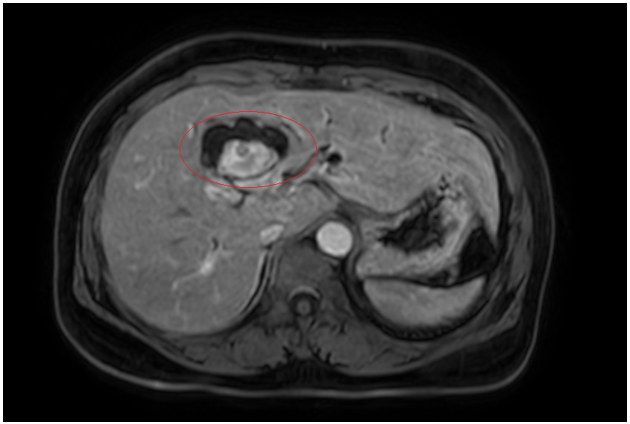

Hình 1. Hình ảnh sỏi đường mật tạo ổ áp xe gan - đường mật gan trái (vòng tròn màu đỏ). Giãn nhẹ đường mật trong gan hai bên. Dày thành nhẹ ngã ba đường mật trên phim chụp cắt lớp vi tính.

Đánh giá tổn thương trên phim chụp cộng hưởng từ: Nhu mô hạ phân thuỳ IV có ổ tổn thương dạng dịch, kích thước 38x52mm, trong có vài sỏi, sỏi lớn nhất kích thước ~27x37mm, có thông với nhánh đường mật gan phải lân cận, ngấm thuốc viền sau tiêm, chèn ép ngã ba đường mật, gây giãn đường mật trong gan hai bên

Hình 2. Hình ảnh giãn khu trú đường mật gan trái, tạo cấu trúc dạng nang và sỏi đường mật bên trong( vòng tròn đỏ), chèn ép kèm giãn đường mật trong gan hai bên trên phim chụp MRI